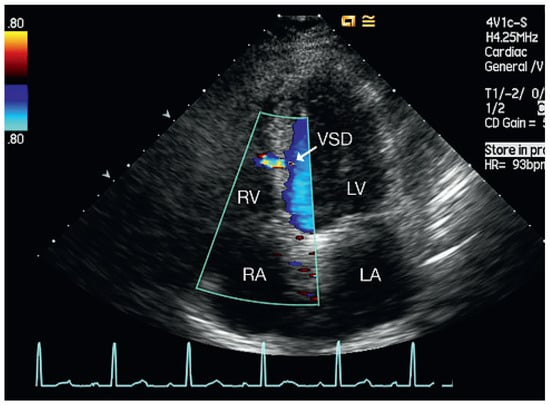

Muscular Ventricular Septal Defect After Mitral and Aortic Valve Replacement